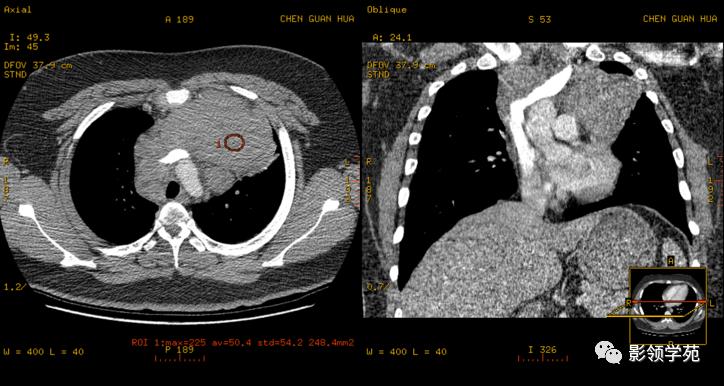

体检发现纵隔肿块

密度均匀,强化均匀

恶性胸腺瘤

穿刺证实恶性胸腺瘤,伴有纵隔淋巴结肿大